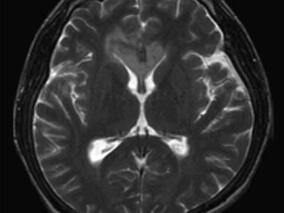

1小时条评论52岁女性,受到惊吓后发生认知障碍且进展迅速。多次检查头颅MRI,显示大脑半球多发性病灶。磁共振波谱分析(MRS)检查显示胆碱(Ch)波峰增高,可见乳酸(La)波峰。提示病灶部位新陈代谢增快,同时伴有组织缺氧表现,提示肿瘤?线粒体脑病?最终左侧开颅颞叶病变活...